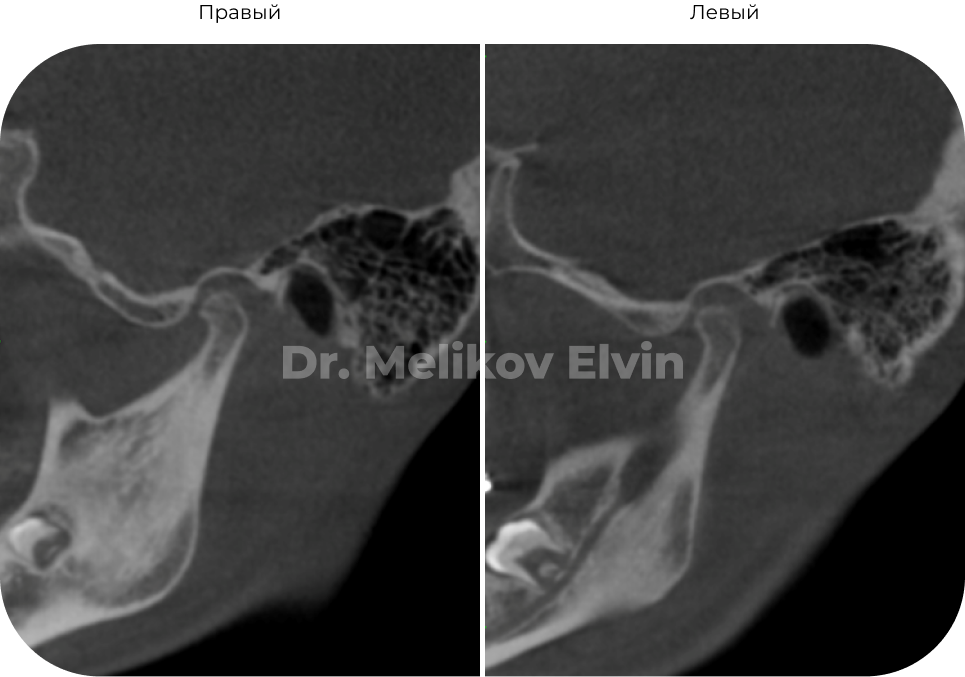

Компьютерная томография ДО.

Компьютерная томография ПОСЛЕ.

Декомпрессия в суставе, восстановилась трофика и целостность кортикальной пластинки.